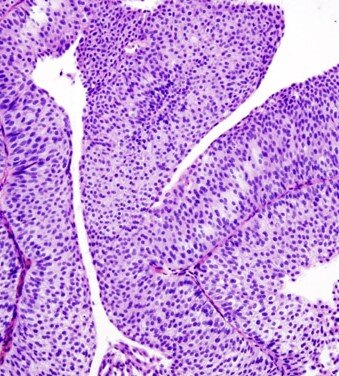

Если опухоль является инвазивной, но не распространяется за пределы мочевого пузыря, 5 летняя выживаемость составляет 70%.

Однако если опухолевые клетки мигрируют в окружающие ткани (регионарные лимфатические узлы) и распространяются на отдаленные органы, 5 летняя выживаемость снижается до 35% и <10%, соответственно. Поэтому раннее выявление рака мочевого пузыря без проксимального и дистального метастазирования имеет решающее значение для повышения выживаемости пациентов с опухолевым процессом.